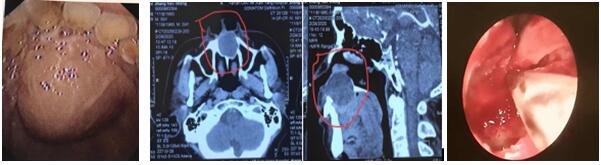

患者,男,59岁,因“发现口腔内肿物3月”入院,肿物累及鼻底,并导致鼻底严重隆起,经上颌骨CT三维重建检查,肿物大,且口内粘膜因肿物压迫已很菲薄,还合并肾病综合症,口服激素一年余。住院后张立刚主任组织术前讨论,认为患者如行传统经唇龈切口手术方式,极易导致伤口感染或不愈合,引起囗腔鼻腔漏,给患者带来灾难性后果。经查阅文献,结合自身坚实的鼻内镜技术基础,决定行经鼻内镜鼻底上颌骨囊肿摘除术。手术取鼻底小切口入路,切开黏膜后即见大量粘液溢出,清理后见口腔面黏膜菲薄,透光,与术前评估一致,遂将囊肿切除,等离子彻底止血,为防止压迫导致口腔鼻腔漏形成,摒弃传统的碘仿纱条压迫两周的观念,术腔仅填塞可吸收明胶海棉,避免因填塞导致术后剧烈头痛等不适。术后检查见鼻腔结构完整,口内包块明显缩小,鼻面部无任何不适。

上颌骨囊肿在临床上并不罕见,其发病隐弊,多无症状,当发现上颌骨囊肿时,其上颌骨破坏程度已相当严重。传统手术方式创伤大,上颌骨骨质暴露多,术后出现头痛、流泪、面部肿胀及麻木,易增加感染机会。